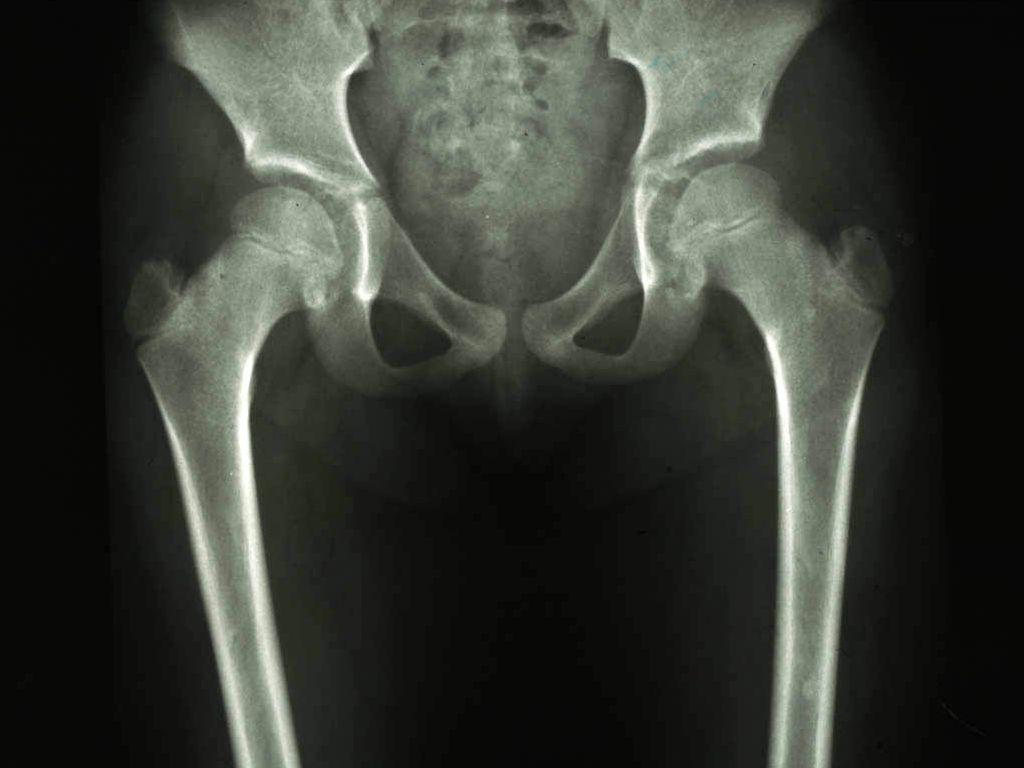

papeltjes, lijkend op pseudoxanthoma elasticum. Osteopoikilosis is de aanwezigheid

van multipele kleine ovale of ronde wit oplichtende osteosclerotische haarden

in de botten, vooral in de carpale en tarsale botjes maar ook in de lange beenderen

en het bekken.

X-handen: Hellerhoff

- Wikimedia (Creative Commons License

3.0).

Diagnostiek:Biopt om de aanwezigheid van abnormale

elastine vezels aan te tonen. X-handen, polsen, voeten, enkels en bekken met

vraagstelling osteopoikilosis.